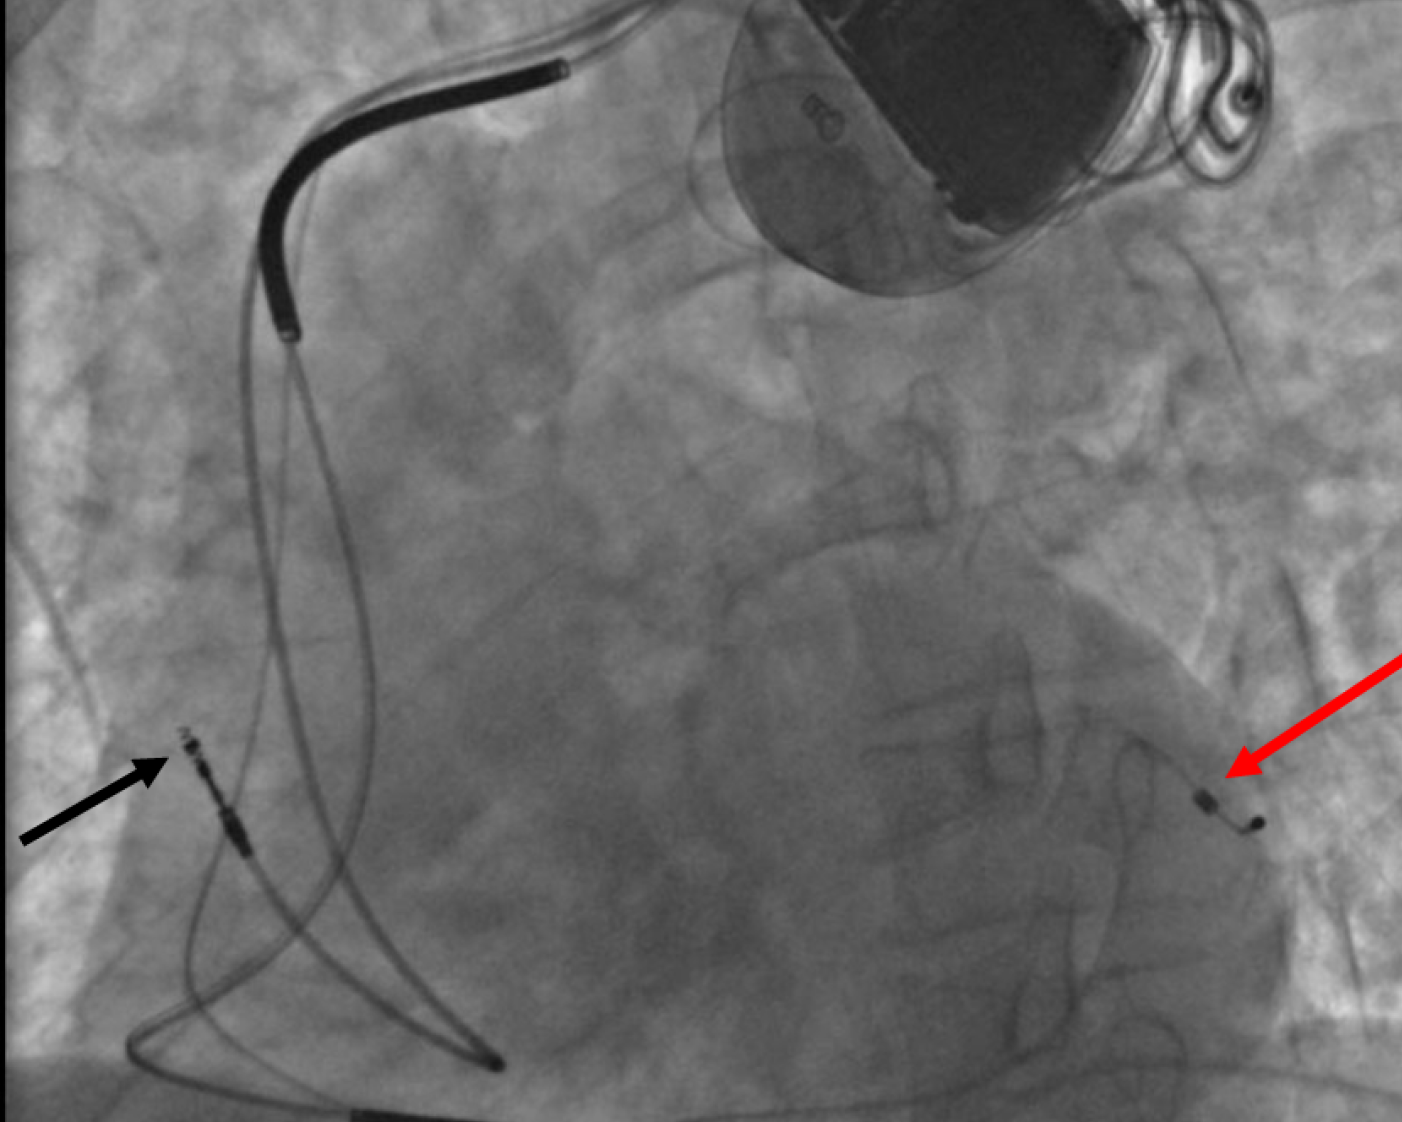

Advanced pacemaker procedures with precise placement and monitoring to improve heart rhythm and recovery.

Advanced ICD implantation to manage dangerous heart rhythms with precision and monitoring for better outcomes.

Advanced CRT implantation to improve heart coordination with precision and monitoring for better outcomes.